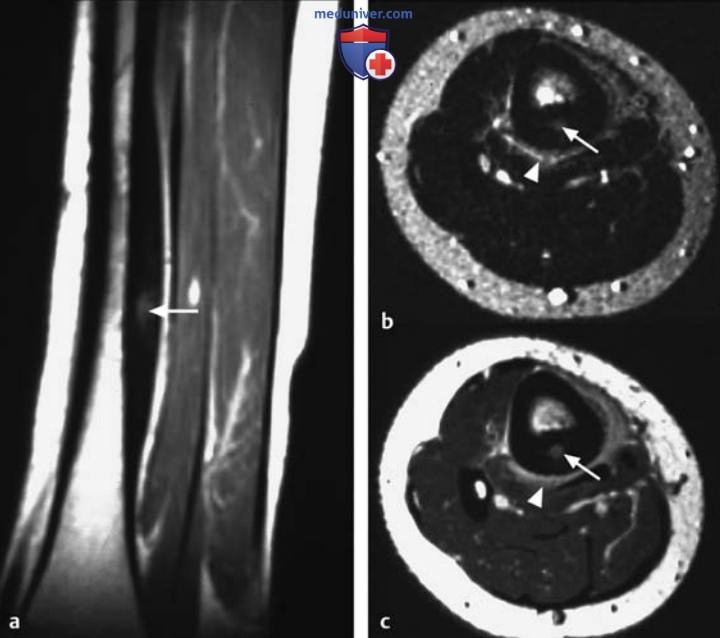

Рисунок 10. а, b Аневризматическая костная киста проксимального отдела малоберцовой кости.

а Т2в-SЕ-изображение в аксиальной плоскости.

b Т1в-SЕ-изображение после контрастирования.

Определяется кистозное поражение с экспансивным ростом, множественными септами, уровнями жидкости и гипоинтенсивным окаймлением на Т2в-изображениях. Отмечается интенсивное усиление сигнала от стенки кисты на Т1в-изображениях после контрастирования. Заметьте отек окружающей мышечной ткани (головки стрелок) и значительное вздутие кости.